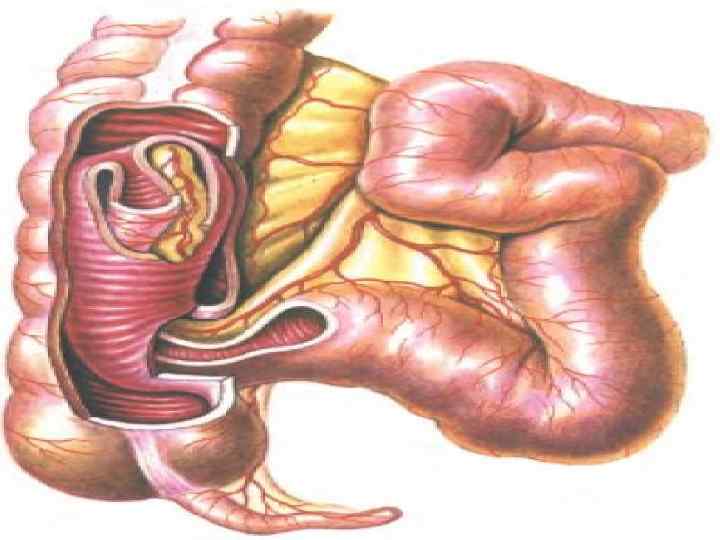

Илеустың жедел, созылмалы және ауыспалы түрлерін бөледі. Жедел илеус - ойда жоқта, бұған дейін дені сау адамда басталып, оның жағдайы тез ауырлайды. Созылмалы илеусқа бәсендеп өсетін ішек ісігі, ал ауыспалы түріне ішектің бұралуы үшыратады. Ішектің толық бітелуі немесе жартылай бітелуі мүмкін. Жартылай бітелуінде нәжіс және газ аздап шығады. Ішек түйілуінің барлық түрлерін механикалық және динамикалық деп екі топқа бөледі. Механикалық деп ішектің бұралуында, қысылуында, бітелуінде, сырттан басылуында байқалатын түрін атайды. Механикалық илеус - странгуляциялық және обтурациялық болып екіге бөлінеді. Странгуляциялық түрінде ішек сыртқы себептен түйіледі. Бұңда ішек ғана емес, оның шажырқайы қысылып қан айналысы бүзылады да қысылған ішектің некрозы басталады.

Странгуляцияға ішек бұралуы, байлануы, қысылуы, күрмелуі себеп болады. Обтурациялық түрінде ішек ісікпен, аскаридамен, дәкелі құрғатқыш (операцияда ұмытылған) бітеледі. Қан айналысы онша бұзылмайды. Өйткені шажырқай қысылмайды. Ішек түйілуінің келесі себебі инвагинация - ішекке ішек еніп оның бітелуіне қоса шажырқайдың қысылып, қан айналысы бұзылуы байқалатындығынан илеустің бұл түрінде обтурация және странгуляция қоса байқалады. Ішектің қабырғасының тегіс етінің әлсізденуіне байланысты кездесетін ішек түйілуі динамикалық деп аталады. Илеустің бұл түрін тырысқан және салды деп екіге бөледі. Спастикалық түрі - ішек қабырғасының тырысуынан оның өзегі тарылуымен байланысты болса, паралитикалық илеусте ішек созылған, өзегі кеңіген, оның тонусы - қозғалуы нашарланған.

г) Бұралу (volvulus) - ішек өзінің түбірінде айналып бұралады. Бұралу ішектің ең қозғалғыш бөліктерінде ащы ішек пен сигма ішегінде кездеседі. Кан айналысының тоқтауы және ішек түйілуі бұралу мөлшеріне байланысты. Ішектің 1800 бұралуы ішек түйілуіне әкелмейді. 270 -3800 бұралу ішекті және шажырқай қан тамырларын толық бітеп, тез арада ішек гангренасына әкеледі. д) Жабысқақтар және тыртықтар - ішектегі қабыну үрдісінен және операциядан соң пайда болады. е) Күрмелу (Nodus) - странгуляциялық ішек түйілуінің ең ауыр түрі. Күрмелу ащы ішек арасында, немесе ащы және тоқ ішек арасында пайда болады. Бұндай науқастар 12 сағат арасында өліп кетуі мүмкін. Бұл байланған, күрмелген ішектің шапшаң гангренаға шалдығуымен байланысты. Күрмелуге ішектің көп бөлімінің қатынасуы күшті экссудацияға, шокке соғады. Егер ішектің көп бөлшегі күрмелсе метеоризм шамалы. Ішек күрмелуіне ұшырағандардың өлімі 40 -50% жетеді.

. Ащы ішектің (заворот) айналуы . Ішектің ішекке енуі – (инвагинация).